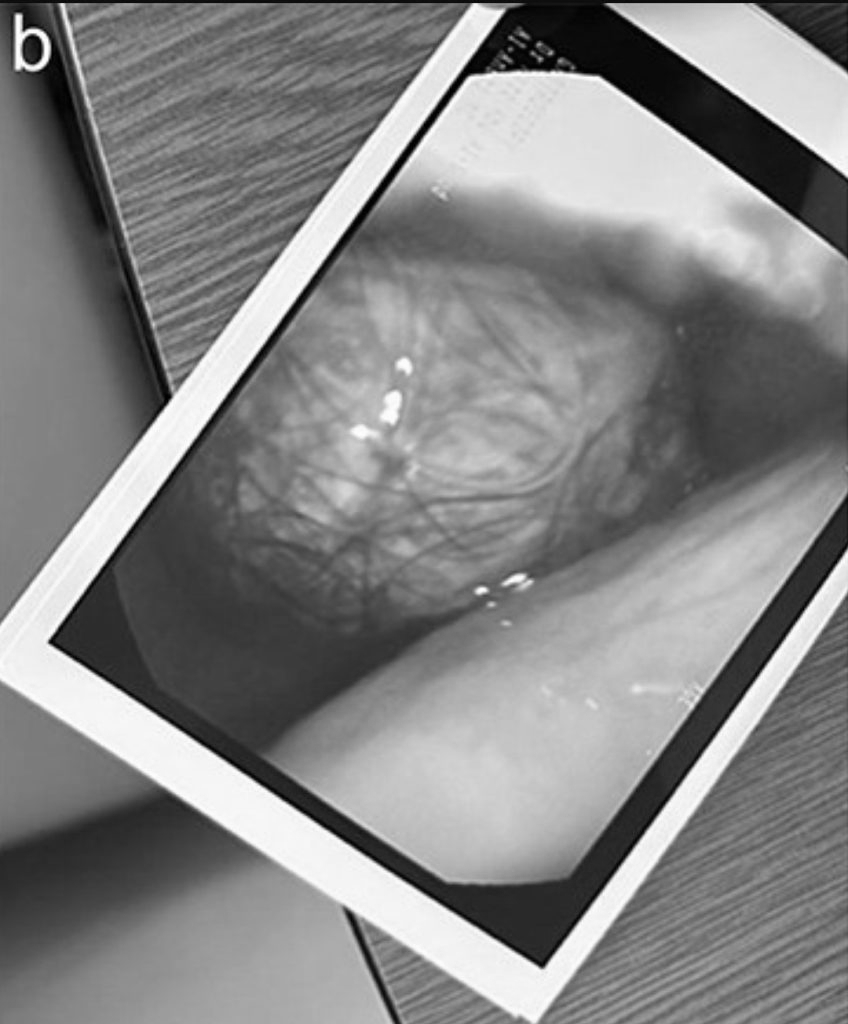

Do kích thước của khối tóc, việc loại bỏ bằng phương pháp nội soi là không thể nên nữ bệnh nhân đã phải trải qua phẫu thuật mở dưới gây mê toàn thân.

Thiếu nữ 17 tuổi liên tục đau bụng, nôn ói, bác sĩ sốc nặng khi phát hiện "bí mật" đáng sợ- Ảnh 2.

Búi tóc lớn được lấy ra cẩn thận và vẫn còn nguyên vẹn. Và sau 3 giờ đồng hồ, dị vật đã được lấy ra an toàn.